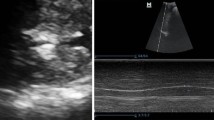

The high-resolution ultrasonic diagnostic apparatus (Aixplorer, Supersonic Imagine, Provence, France) was used, with a 4–15 MHz frequency linear array probe. Each subject was instructed to remain in the left lying position. The physician placed the probe under the rib between the anterior to mid-axillary line and approximately the 6th to 12th intercostal space to allow for the probe to display the diaphragm to the greatest extent (Fig. 1). The gain was adjusted, and the depth was checked. After the image of the right diaphragmatic rib of the examinee became stable, the SWE mode was switched, and the elastic range was adjusted to 0-160 kPa. When the subject was calmly holding their breath at the end of inhalation, the elastic modulus of the diaphragm and intercostal muscles in the ROI (region of interest) was measured by using Q-BOX. When measuring the diaphragm, a circular area with a diameter of 1 mm was selected as the ROI. The elastic modulus of the diaphragm was measured three times, and the average value was taken (Fig. 2). The subject was instructed to move to a supine position, and the physician placed the probe on the intercostal muscles of the front chest wall to obtain images of the intercostal muscles (Fig. 1). The subject was then asked to hold his or her breath at the end of inhalation. After the image became stable, the SWE mode was turned on, and the elastic modulus was measured. The ROI was set to a circle with a diameter of 2 mm, and the average was taken after 3 measurements (Fig. 3). Similar to the measurement method of An [22], the diaphragm excursion (DE) and diaphragm thickening fraction (TF) were measured at tidal inspiration and at maximal deep inspiration. Pulmonary function tests were performed in accordance with the standards of the European Respiratory Society [23], and the FEV1, forced vital capacity (FVC), FEV1/FVC, inspiratory capacity (IC), functional residual capacity (FRC), residual volume (RV), total lung capacity (TLC) and RV/TLC were recorded.